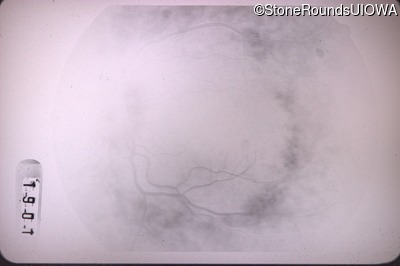

Age at visit: 43 years (Visit 2)

This 43 year old woman first experienced a slight loss of visual acuity at age 23. Fluorescein angiography at that time revealed some vascular leakage from the optic discs and peripheral retina. The maximum combined response of the ERG revealed a selective loss of the b-wave.